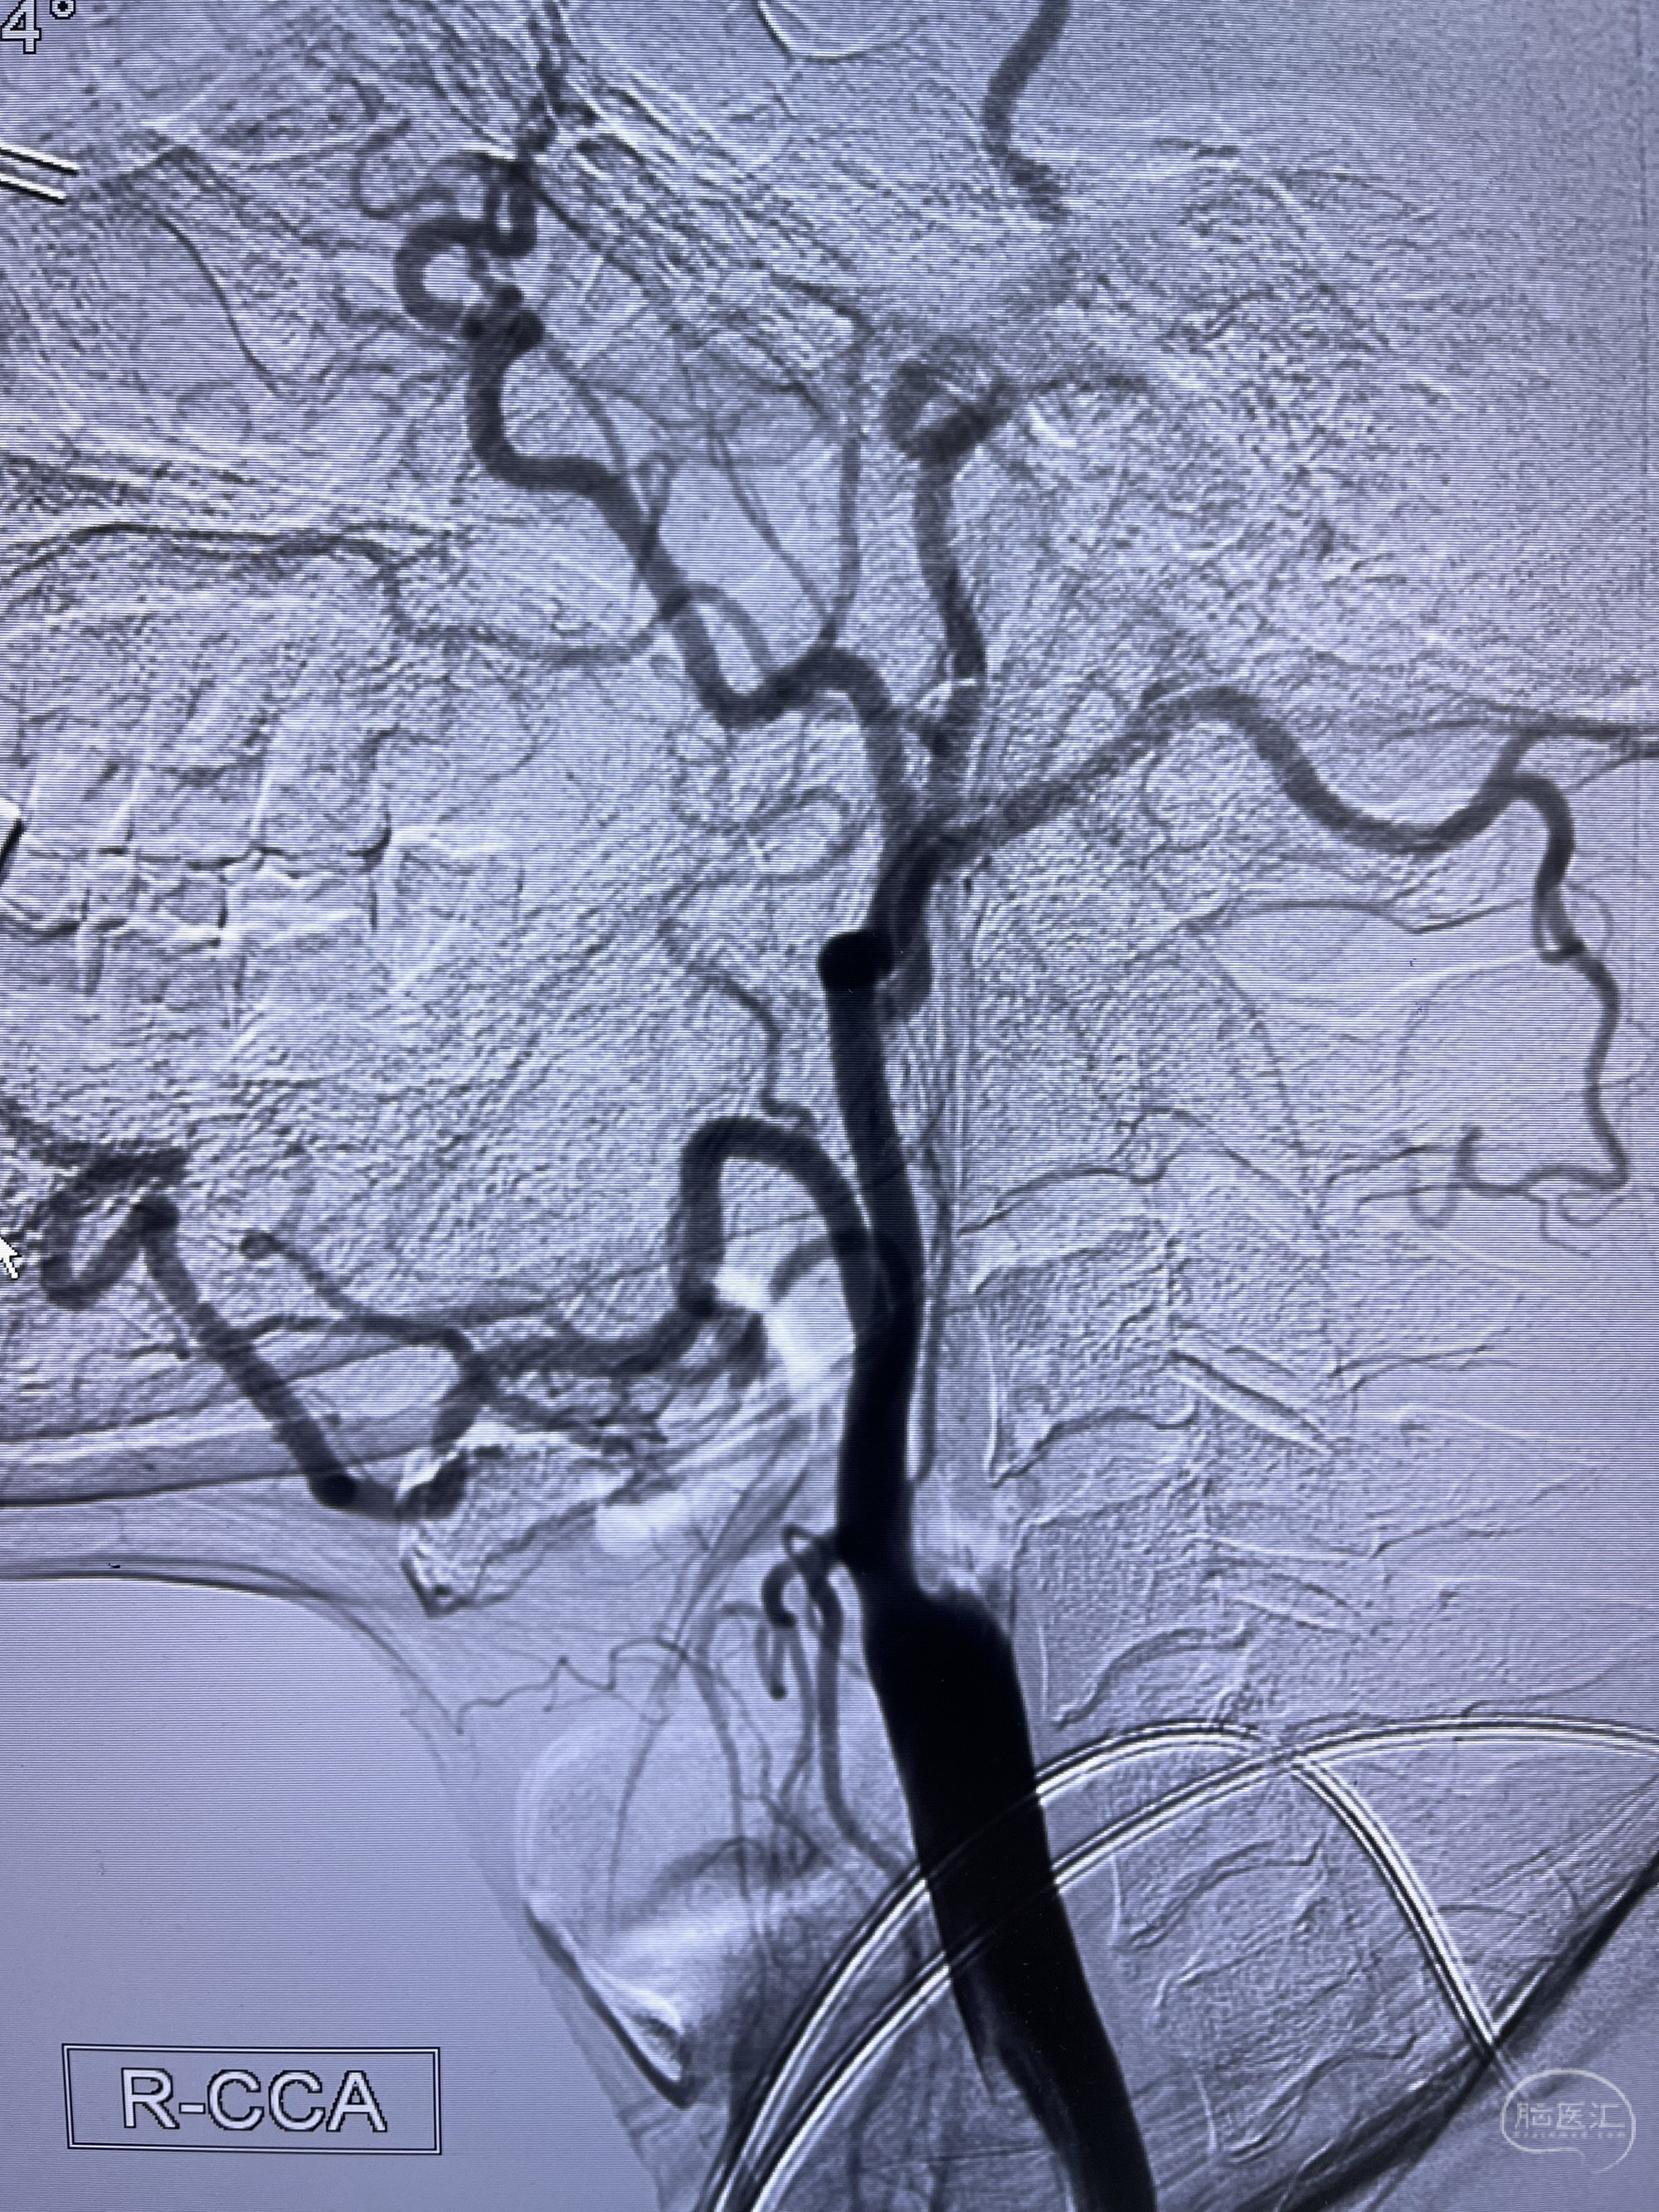

脑血管造影2023.03.06:右侧颈内动脉颈段至岩骨段闭塞,可见后后循环通过原始三叉动脉吻合代偿至海绵窦段,后交通区可见囊状造影剂填充影,左侧锁骨下动脉呈“残端”改变,呈“右侧颈总动脉支架成形术后改变”,支架内血流通畅,可见后交通吻合显影至左侧大脑后动脉,并可见左枕动脉吻合椎动脉至锁骨下动脉

2023-03-06DSA:

1.右侧颈内动脉及左侧锁骨下动脉闭塞

2.右侧颈内动脉由后循环经右侧后交通动脉前向代偿显示

3.右侧颈内动脉眼动脉段近后交通动脉处重度狭窄伴前壁不规则动脉瘤

4.右侧颈外动脉可见经由右侧脑膜中动脉吻合显影右侧眼动脉及颈内动脉

5.左侧颈总动脉起始部支架术后

1.箭头处为右侧颈内动脉后交通动脉处重度狭窄,狭窄前壁为不规则动脉瘤;

2.狭窄远端颈内动脉由左侧颈内动脉经左侧后交通动脉—基底动脉顶—右侧后交通—右侧颈内动脉—右侧大脑中动脉途径代偿

左侧颈内动脉经左侧后交通动脉—基底动脉顶—右侧后交通—右侧颈内动脉—右侧大脑中动脉途径代偿